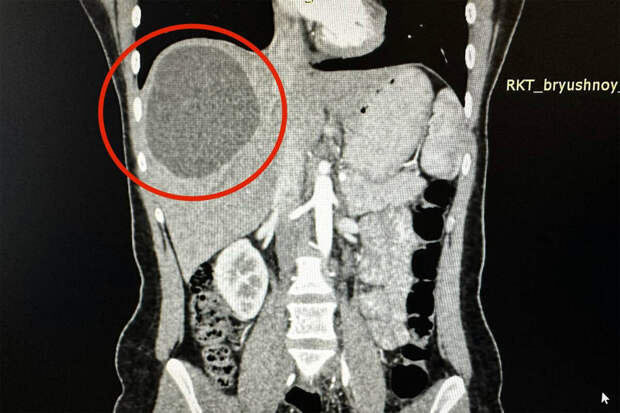

По информации Telegram-канала, девушка обратилась в Республиканскую клиническую больницу и пожаловалась на сильную боль в области живота. Врачи обследовали пациентку и обнаружили скрутившихся в кисту размером 15 на 20 сантиметров паразитов в ее печени.

Сначала медики назначили россиянке химиотерапию, а через три месяца провели операцию по удалению клубка червей. Оказалось, что паразиты значительно "подъели" печень девушки. Вместе с ними пришлось удалить почти треть органа.